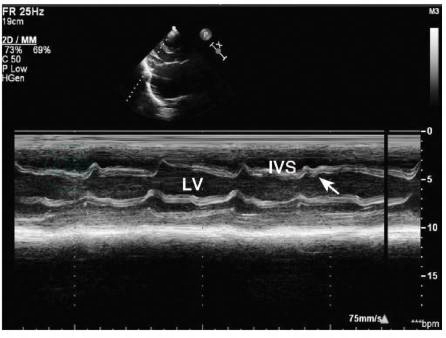

M型、二维超声心动图及多普勒超声心动图是临床最常用的无创检测手段。典型的表现为心包增厚、粘连(图2),心脏变形,室壁活动减弱,室间隔舒张期矛盾运动,即室间隔抖动征(图3),下腔静脉增宽且不随呼吸变化。

图3 缩窄性心包炎室间隔运动异常